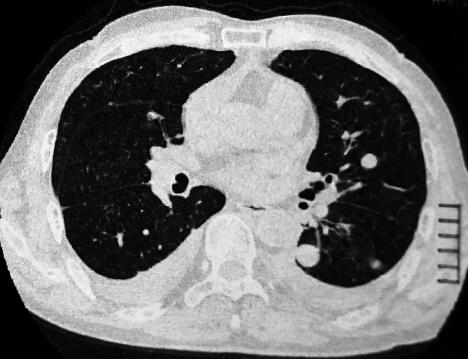

患者为农民,主要从事家务。既往身体健康,无呼吸系统疾病。半年前开始出现少量痰中带血,无明确诱因,其后咯整口鲜血,无胸痛,有轻度活动后气短。于当地诊所检查,胸部CT示双肺多发磨玻璃影,团片影、边缘呈晕轮征(图1)。给予抗感染及止血对症治疗(具体不详),咯血有所减轻。两个月前,患者为明确诊断就诊于我院,进行免疫生化检测时发现P-ANCA(±),诊断为弥漫性肺泡出血,肺血管炎可能性大,止血治疗的同时给予甲泼尼龙治疗,咯血症状消失,气短有所缓解,复查胸部CT:晕轮征及磨玻璃影有所吸收(2)。继续甲泼尼龙24mg,每日1次,院外口服治疗。患者应用甲泼尼龙1个月后减量至每日20mg,但此后应用不规范,剂量波动于每日16~20mg。患者于入院前半个月再次出现痰中带血,伴胸闷气短,咯血量有增加趋势。

图2

6.胸部影像学:肺动脉CTA未见血管充盈缺损,胸膜下见双肺多发球形结节影,周围伴晕轮征,肺内见多发磨玻璃影,双侧胸腔积液,少量心包积液(图3)。

动脉血氧分压降低,结合患者的病史和体格检查结果,提示患者肺泡出血面积较大,换气功能障碍,因此患者自觉呼吸困难。风湿免疫相关抗体均为阴性,尚不支持肺血管炎的诊断。另外,肺内原有小结节在短时间内迅速增大,并出现双侧血性胸腔积液,心包积液用血管炎也较难解释,应进一步寻求病理诊断。

本例患者病初磨玻璃影和晕轮征,结合咯血病史,考虑可能的诊断为血管炎是正确的。同时需要注意晕轮征缺乏特异性,但对缩小鉴别诊断范围有一定的帮助。另外,影像学需要动态评估,第一次就诊,在激素治疗后晕轮征有所吸收,而结节影没有吸收,应引起足够的重视去鉴别恶性疾病,引起晕轮征的常见恶性疾病包括:细支气管肺泡癌,肺鳞癌,肺腺癌,血管肉瘤,骨肉瘤,Kaposi肉瘤等。在诊断不确切时,如果病情允许,应积极进行组织病理学检查。